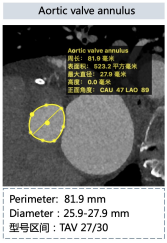

主动脉CT

瓣膜形态

入路状况

结构上,该病例为Type0型二叶瓣,瓣叶钙化、增厚严重,且流出道呈喇叭口型。考虑远期效果,为避免瓣膜选择过大打开不良造成瓣膜过早衰败,可参照瓣上狭窄结构Downsize选择TAV24瓣膜;同时为了避免瓣膜移位及瓣周漏,应采取高位定位释放的策略,释放过程中应留意输送系统及导丝的牵拉稳定瓣膜位置,如遇瓣膜位置不佳,及时应用可回收功能进行再次定位释放。双侧入路直径充足,但双侧股动脉分叉均较高,可考虑主入路外科切开后于稍高处穿刺。

全麻下,以右侧股动脉为主入路(外科切开后穿刺),使用22mm球囊预扩张,植入TAV24型号Vitaflow瓣膜。